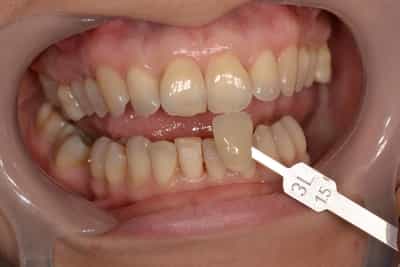

Eclaircissement Dentaire ou Blanchiment

L’éclaircissement dentaire est une technique consistant à rendre aux dents une couleur plus harmonieuse, plus en adéquation avec l’image que le patient veut donner de lui. Le blanc des yeux est une référence. A l’échelle du visage, la blancheur de la sclérotique de l’oeil (blanc des yeux) fait ressortir la couleur jaune des dents. Pour une meilleure harmonie, il faut aligner ces deux couleurs. Si les dents sont moins lumineuses, l’éclaircissement va améliorer l’apparence. Après éclaircissement, cette différence s’atténuera et donnera une harmonie du visage.

Souvent, à partir d’un certain âge, les dents changent de couleurs. Ces changements peuvent être dûs à des colorations extrinsèques. Dans ces cas, un simple nettoyage-polissage peut suffire à y remédier.

Dans d’autres cas, il s’agit d’une usure de l’émail. L’émail est responsable de la luminosité de la dent, et son usure a tendance à révéler la couleur de la dentine sous-jacente. Elle peut être marron, jaune, grise, orange… L’éclaircissement agit sur les colorations intrinsèques et extrinsèques, en surface et en profondeur.

Souvent, il sera plus judicieux de réaliser un éclaircissement avant un travail prothétique, ou des composites antérieurs, car les techniques d’éclaircissements ne sont pas actives sur les céramiques ou les composites.

On distingue deux types d’éclaircissement:

-le blanchiment externe : il concerne les dents vivantes et consiste à l’application d’un gel éclaircissant sur l’extérieur des surfaces dentaires. Cette technique de homebleaching nécessite obligatoirement l’accompagnement de votre dentiste. Il faut savoir gérer les éventuelles sensibilités pouvant apparaitre dans de rares cas. Le blanchiment doit être encadré dans son protocole et sur toute sa durée.

-le blanchiment interne : il concerne les dents dévitalisées (mortes). La technique est différente et consiste à déposer directement dans la dent un produit sur une période déterminée.

L’éclaircissement dentaire connait ses limites. On n’en réalisera pas chez la femme enceinte. Il n’est pas efficace sur les colorations dûes aux amalgames dentaires, couronnes ou matériaux d’obturation. Pour toutes les taches de fluorose ou de MIH (hypominéralisation de l’émail au niveau des incisives et molaires), l’éclaircissement dentaire n’est qu’un préalable à un autre traitement.